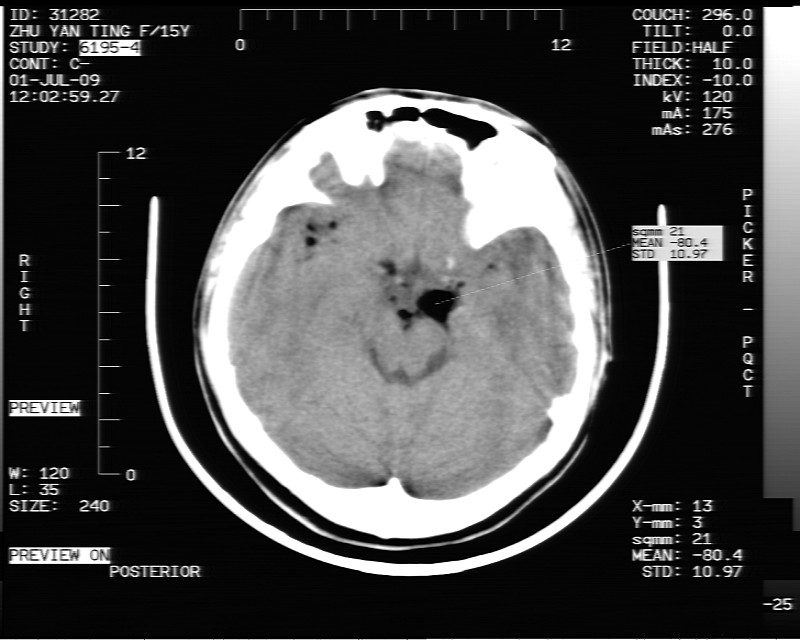

以下是引用随光逐影在2009-7-1 16:26:00的发言:[br]鞍上池表皮样囊肿或含脂肪类肿瘤破裂并化学性脑炎?

以下是引用余辉在2009-7-1 17:20:00的发言:[br]病变ct值-20至-80[br]考虑脑内脂肪瘤破裂,瘤主体应该在右侧桥小脑角池及鞍上池[br]鞍上池病灶面积较大,ct值应该能够测准,应此病灶应该就是脂肪密度,病灶密度有ct值-20至-80hu,为成熟脂肪密度,因此考虑脂肪瘤,也不除外其他含成熟脂肪的病灶[br]皮样囊肿密度应该稍高一点

以下是引用zjzjr在2009-7-1 16:52:00的发言:[br]支持皮样囊肿破裂.,表皮样囊肿一般密度均高.[br][br][本贴已被 zjzjr 于 2009-7-1 16:52:29 修改过]